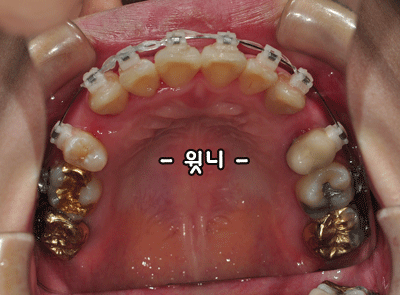

▼ ▼윗니▼ ▼